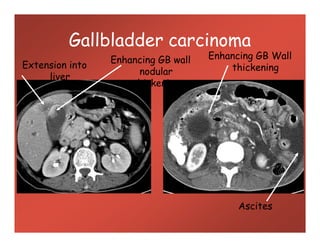

Gallbladder carcinoma

Enhancing GB Wall

thickeningExtension into

liver

nodular

thickening

Ascites